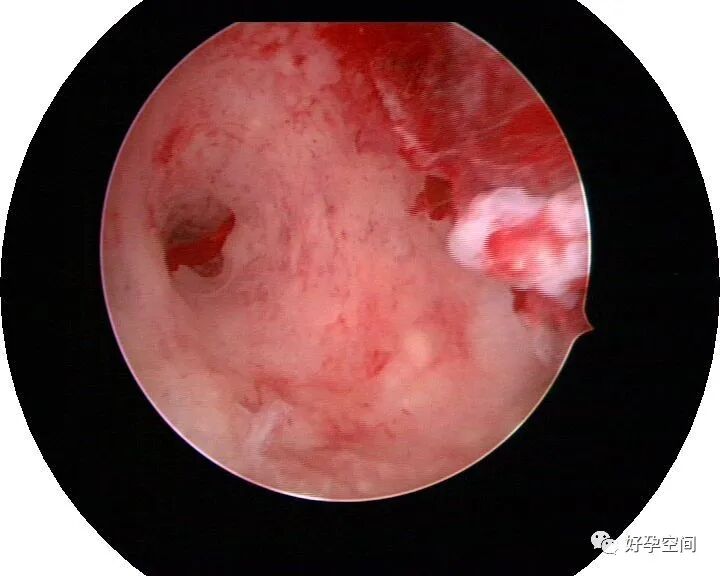

病例20:宫腔粘连变形狭窄内膜瘢痕及出血